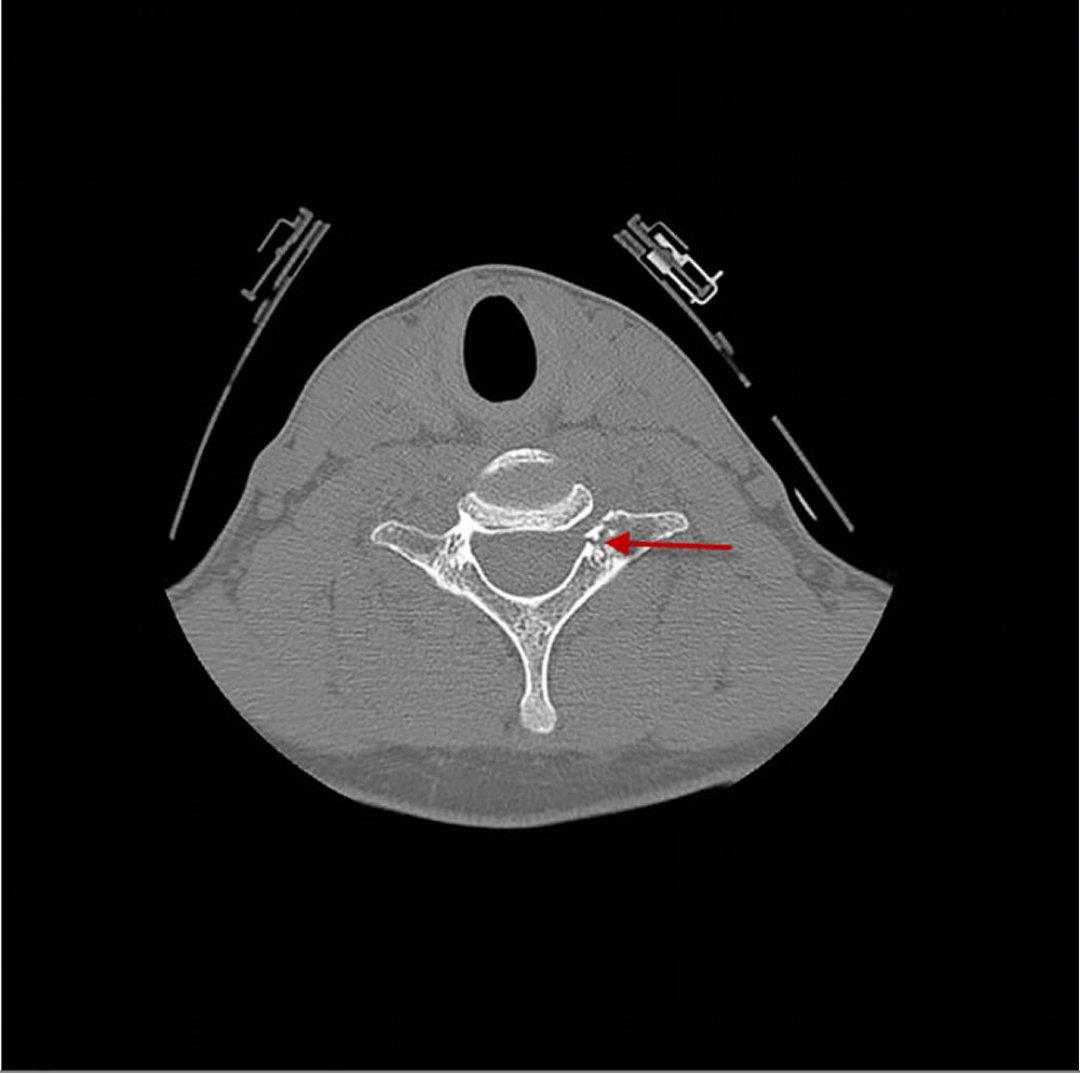

Vértebra cervical fracturada

Fractura del cuerpo vertebral cervical

Si se identifica una fractura, una subluxación o una lesión ligamentosa de la columna cervical, generalmente se justifica un estudio vascular (típicamente, angiografía por TC) para descartar lesiones concomitantes en la arteria carótida o la arteria vertebral.